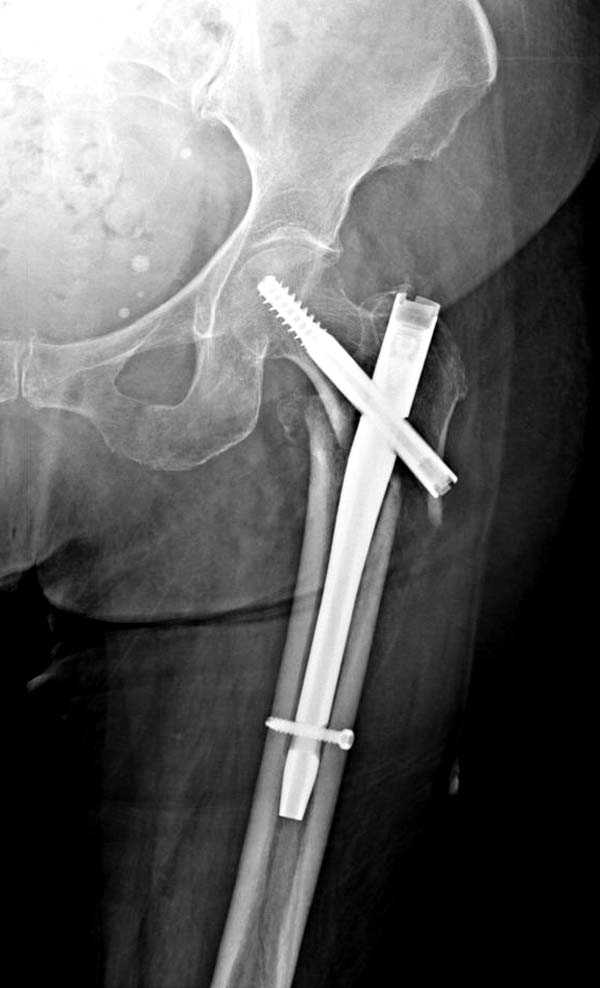

Здесь представлен случай, где в послеоперационном периоде обнаружена техническая ошибка, Gamma 3 установлен с нарушением методики. Больная в 91 лет, прооперирована через день после поступления и выписана через 48 часов.

При первом послеоперационном поликлиническом осмотре больная предъявила жалобы на боли в бедре. В серийных снимках обнаружен продольный перелом верхнего отдела бедра.

Считаем, что техническая ошибка произошла во время установки гвоздя, когда рассверливанию канала не уделили должного внимания. Канал остался узковат, и гвоздь был забит с силой. Полная нагрузка конечности приостановлена на две недели, и боли в конечности изчезли. Больная начала нагрузку и перелом срастается.-- Djoldas Kuldjanov, M.D.Associate ProfessorDepartment of Orthopedic SurgerySt. Louis University

I have a different interpretation of this case. I suspect you did not tighten the set screw all the way in order to allow sliding of the lag screw and fracture fragment compression, as you would for a standard intertrochanteric hip fracture. This is a reverse obliquity fracture, so the result is migration of the proximal segment. I doubt reaming the canal would have prevented this. Had the set screw been fully tightened, there would be no postoperative fragment motion.

I looked at the films again and saw that you are referring to the nondisplaced shaft fracture, not the proximal fragment position. Sorry.

Мне думается, что варусное положение проксимального отломка на последующих снимках не более чем проекционный феномен. Раскол же диафиза вдоль, наверняка, связан с чрезмерно насильственным введением штифта. Вообще, при реверсивных, да и обычных вертельных переломах, многие давно отказались от короткой Гаммы в пользу long-версии. Но в любом случае надо быть на 100 уверенным в подготовке канала.

Перелом А3, подвертельный, вероятно, на длинной версии гвоздя такого бы не произошло